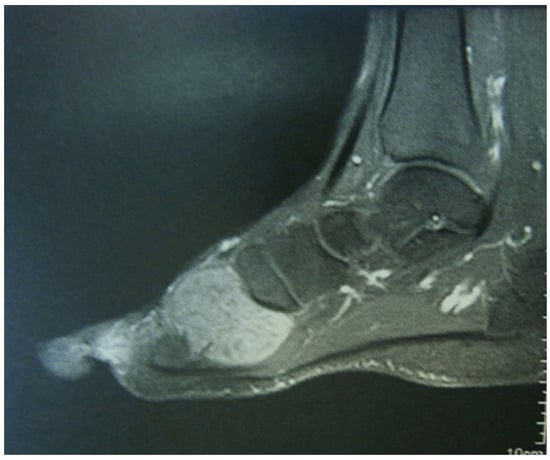

4. Imaging

- Jelinek, J.S.; Kransdorf, M.J.; Utz, J.A.; Berrey, B.H., Jr.; Thomson, J.D.; Heekin, R.D.; Radowich, M.S. Imaging of pigmented villonodular synovitis with emphasis on MR imaging. AJR Am. J. Roentgenol. 1989, 152, 337–342. [Google Scholar] [CrossRef] [PubMed][Green Version]

- Cheng, X.G.; You, Y.H.; Liu, W.; Zhao, T.; Qu, H. MRI features of pigmented villonodular synovitis (PVNS). Clin. Rheumatol. 2004, 23, 31–34. [Google Scholar] [CrossRef]